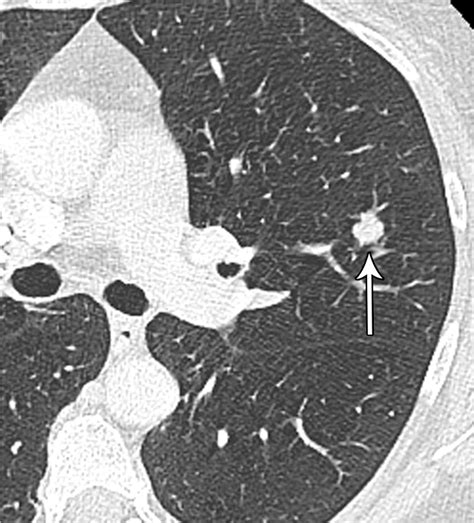

Lung nodules are small, round or oval-shaped growths that appear in the lung tissue. They can be benign or malignant, and their detection often occurs incidentally during imaging studies performed for other reasons. The size and characteristics of these nodules play a significant role in determining the likelihood of malignancy and the need for further evaluation.

The Fleischner Society Criteria classify lung nodules into three main categories based on their size:

• Solid Nodules: These are completely opaque and have a well-defined border.

• Part-Solid Nodules: These have both solid and ground-glass components.

• Ground-Glass Nodules: These are hazy areas of increased lung attenuation without obscuration of the underlying bronchial structures or vessels.